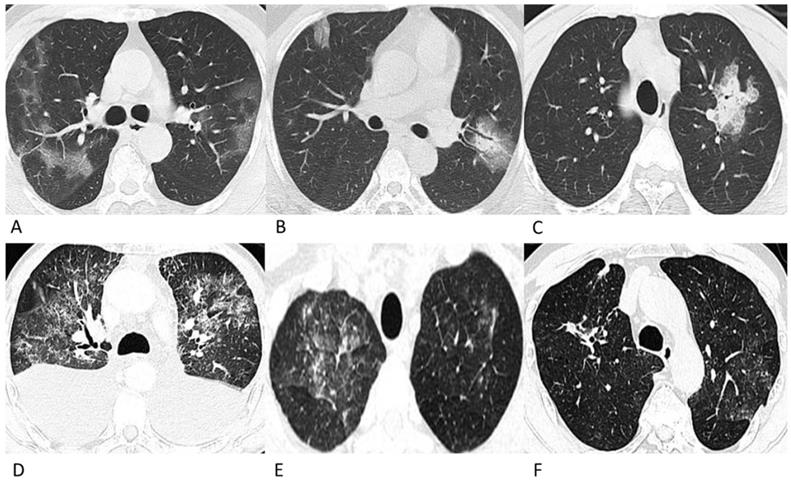

Figure 2

Representative chest CT images of COVID-19 pneumonia with halo sign (A) and reversed-halo sign (B). (A) A 28-year-old man who worked in Wuhan had a fever and cough on admission. A Patchy GGO and two mixed GGO nodules are shown in the right upper lobe, one of which with halo sign. (B) A 32-year-old man who lived in Wuhan developed fever and cough. Reversed-halo sign is shown in the right upper lobe.

The proportions of CT features such as interlobular septal thickening, vascular thickening, pleural involvement and fibrous stripes observed in the lymphoma cases were statistically compatible with those observed in the COVID-19 cases (p > 0.05). Air bronchograms were seen much more frequently in COVID-19 patients (45%, 50/112) than in lymphoma patients with pneumonia (5%, 4/75) (p < 0.001). Among these lesions, the halo sign (6%) and reversed halo sign (1%) were observed in several COVID-19 patients (Figure 2), while no halo sign or reversed halo sign was observed in lymphoma patients with pneumonia. The representative follow-up chest CT images of lymphoma patients were shown in Figure 3.

Recent studies have shown that chest CT findings appear earlier than clinical manifestations; therefore, chest CT has been recommended as major evidence for the screening, clinical diagnosis and evaluation of lesion progression and therapeutic effects [17, 18]. The chest CT characteristics of COVID-19 pneumonia in this study were generally consistent with those in previous studies [18-20], with patchy (84%) GGO and consolidated lesions in more than one lobe (83%) in the peripheral lung (53%). Moreover, vascular thickening (54%), air bronchogram (45%), pleural involvement (25%), fibrous stripes (20%), and interlobular septum thickening (8%) were recorded in this group of confirmed cases (Figure 1). It is worth mentioning that among these lesions, halo sign (6%) and reversed halo sign (1%) were observed in several patients, which have also been reported in a few recent studies [21, 22] (Figure 2). The halo sign is defined as GGO surrounding a nodule or consolidation and has been initially described in hemorrhagic nodules, which can be typically observed in invasive fungal infections. This sign could also be seen in cryptococcosis and lung neoplasms [23]. The reversed halo sign refers to a focal rounded area of GGO surrounded by a ring of consolidation, which is typically observed in granulomatous diseases and organizing pneumonia [24]. Moreover, when the reversed halo sign is peripheral and with internal reticulation, this suggests pulmonary infarction, and computed tomography angiography is necessary to evaluate the possible pulmonary embolism [25]. Recently, both organizing pneumonia [26] and pulmonary infarction [27] have been observed in COVID-19 patients, which indicates that organizing pneumonia and pulmonary infarction are potential mechanisms of lung injury in COVID-19. Extensive pathological significance of the two CT manifestations observed in COVID-19 patients warrants further study. Despite the similarities in CT manifestations, the proportion of the relatively limited lesion margin was 82% in our cases of COVID-19 patients, while only 30% lesions were well-defined in a previous study [10]; this may be due to the differences in the evaluation criteria, which refers to the diffusion degree of the lesion in this study.